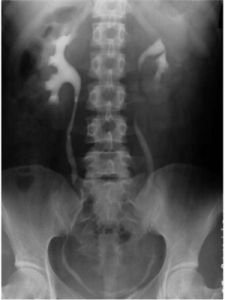

在男性生殖器結核病中,單純睪丸結核者極少。因男性生殖系的結核絕大多數繼發於泌尿繫結核病,如腎結核等。睪丸結核大都是由前列腺、精囊、輸精管、附睪結核相互蔓延而發病,睪丸結核的主要臨床表現,除一般的結核中毒症狀、全身乏力、低熱外,局部為睪丸輕度疼痛,隱痛下墜感,早期不易確診,少數急性發病,多同時有附睪結核存在。可表現為睪丸腫大,疼痛明顯,睪丸腫大,質地稍硬光滑,有時伴有輸精管增厚時,可觸及結節,或成串珠樣等,合併睪丸鞘膜積液時,可觸及睪丸有囊性感,增大明顯。同時並有前列腺、精囊結核時,病人可有尿頻、尿急、尿痛、性慾功能低下、陽痿、遺精、早泄、血精等表現。

睪丸結核的主要臨床表現,除一般的結核中毒症狀、全身乏力、低熱外,局部為睪丸輕度疼痛,隱痛下墜感,早期不易確診,少數急性發病,多同時有附睪結核存在。可表現為睪丸腫大,疼痛明顯,睪丸腫大,質地稍硬光滑,有時伴有輸精管增厚時,可觸及結節,或成串珠樣等,合併睪丸鞘膜積液時,可觸及睪丸有囊性感,增大明顯。同時並有前列腺、精囊結核時,病人可有尿頻、尿急、尿痛、性慾功能低下、陽痿、遺精、早泄、血精等表現。